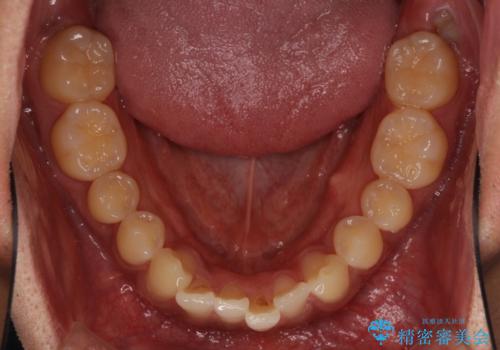

- 前歯のデコボコを気にして来院された患者様です。

主に下顎歯列全体の後方移動とIPR(歯と歯の間を削る)によってデコボコが解消するように設計し、インビザラインにより治療を行うこととしました。

インビザライン矯正特有の、治療後半で前歯のみが強く接触する症状が発現し、咬み合わせ改善に期間を要することとなりました。